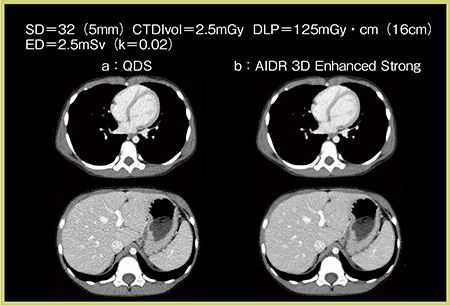

この条件で撮影した造影CT(図2)では,SD32(5mm)でAIDR 3D Enhanced Strongを適用することでストリークアーチファクトも低減され,鎖骨上窩や肺野についても十分診断可能な画像が得られている。造影CTはSD32(5mm)+AIDR 3Dで撮影可能であり,CTDIvolは2.5mGy,EDは2.5mSvとなっている。

図2 症例1:小児体幹部の造影CT

a:QDS b:AIDR 3D Enhanced Strong